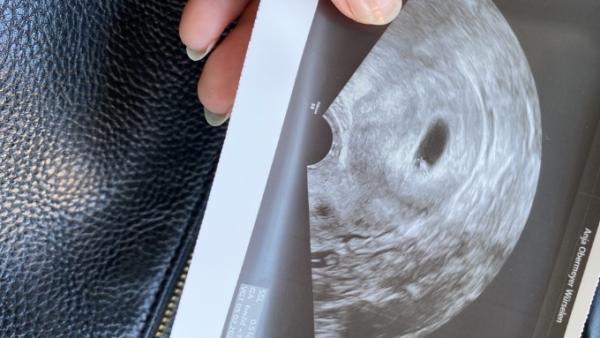

Hat hier jemand Erfahrungen sammeln können und/oder ist gut darin? Ich komme irgendwie immer auf ein anderes Ergebnis

Bild zu Ramzi-Methode - Schwanger - wer noch? Rund um die Schwangerschaft

Junge

In die richtige Richtung Aber ich würde mich da nicht drauf verlassen, meine Tochter wäre laut Ramzi auch ein Junge gewesen

Wie muss man das Bild in die richtige Richtung drehen?